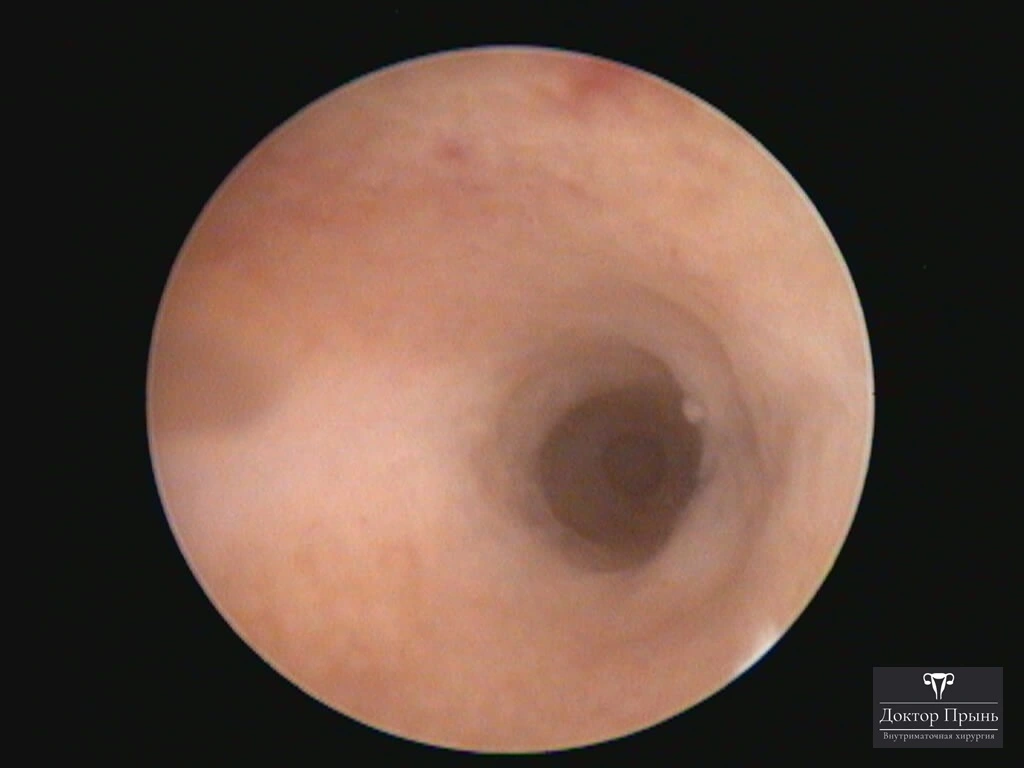

Фотогалерея

Синехии, рассечённые Прынь Д.В.